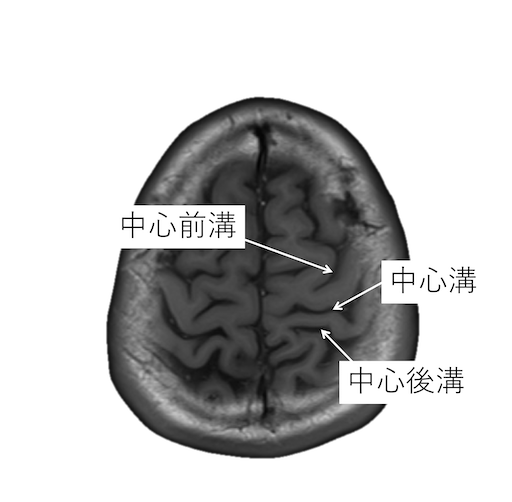

中心溝を同定する際には、以下の4つの原則があります。

・中心前溝は上前頭溝と、中心後溝は頭頂間溝と、連続するが、中心溝が連続する脳溝はない。

・中心後溝の内側端はY字型になり、帯状溝縁部(ちょび髭)は分岐に挟まれる。中心溝の内側端は帯状溝縁部(ちょび髭)のすぐ前にくる。

・脳回の前後幅は中心前回が後回より太い。

・中心前回の手指運動野は後方凸を示す(precentralknob sign)